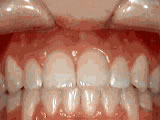

Deep overbite – Lower front teeth bite into palate

This adult patient, age 25, required braces and jaw surgery to correct his severe overbite, with treatment taking two years. His problem could have been corrected without surgery if he had been treated before he was a teenager.